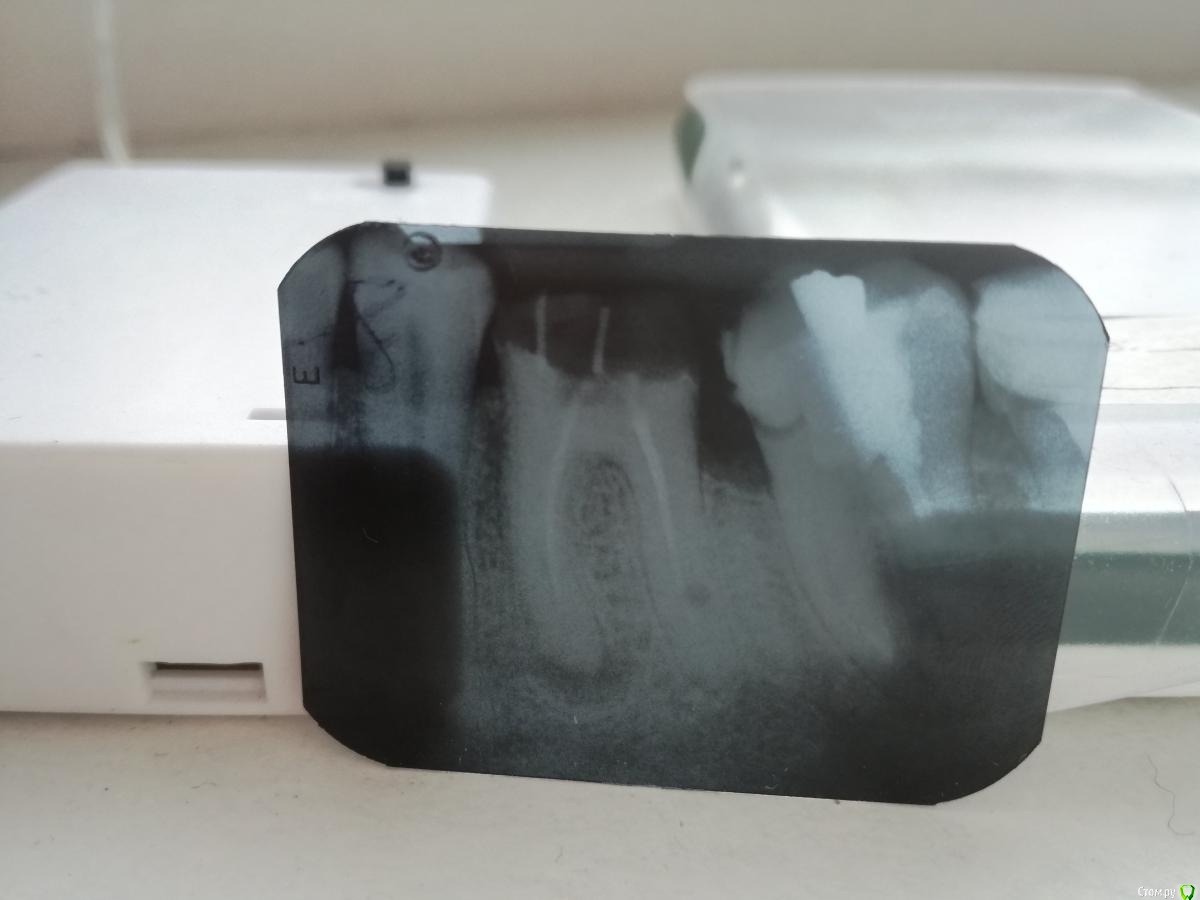

Vlad009 Опубликовано 15 февраля, 2021 Поделиться Опубликовано 15 февраля, 2021 (изменено) Добрый день уважаемые стоматологи!Разрушился под пломбой 36 зуб, думал нужно удалять, стоматолог предложил металлическую коронку на один этот зуб. Имеет ли смысл это делать? Если это возможно, то какого типа коронку лучше и возможно ставить? (предложили металл) Большое спасибо за ответ! Изменено 15 февраля, 2021 пользователем Vlad009 1 Ссылка на комментарий

andraks Опубликовано 16 февраля, 2021 Поделиться Опубликовано 16 февраля, 2021 Перелечить каналы, восстановить, коронка. И в 37 тоже. Цирконий лучше. Ссылка на комментарий